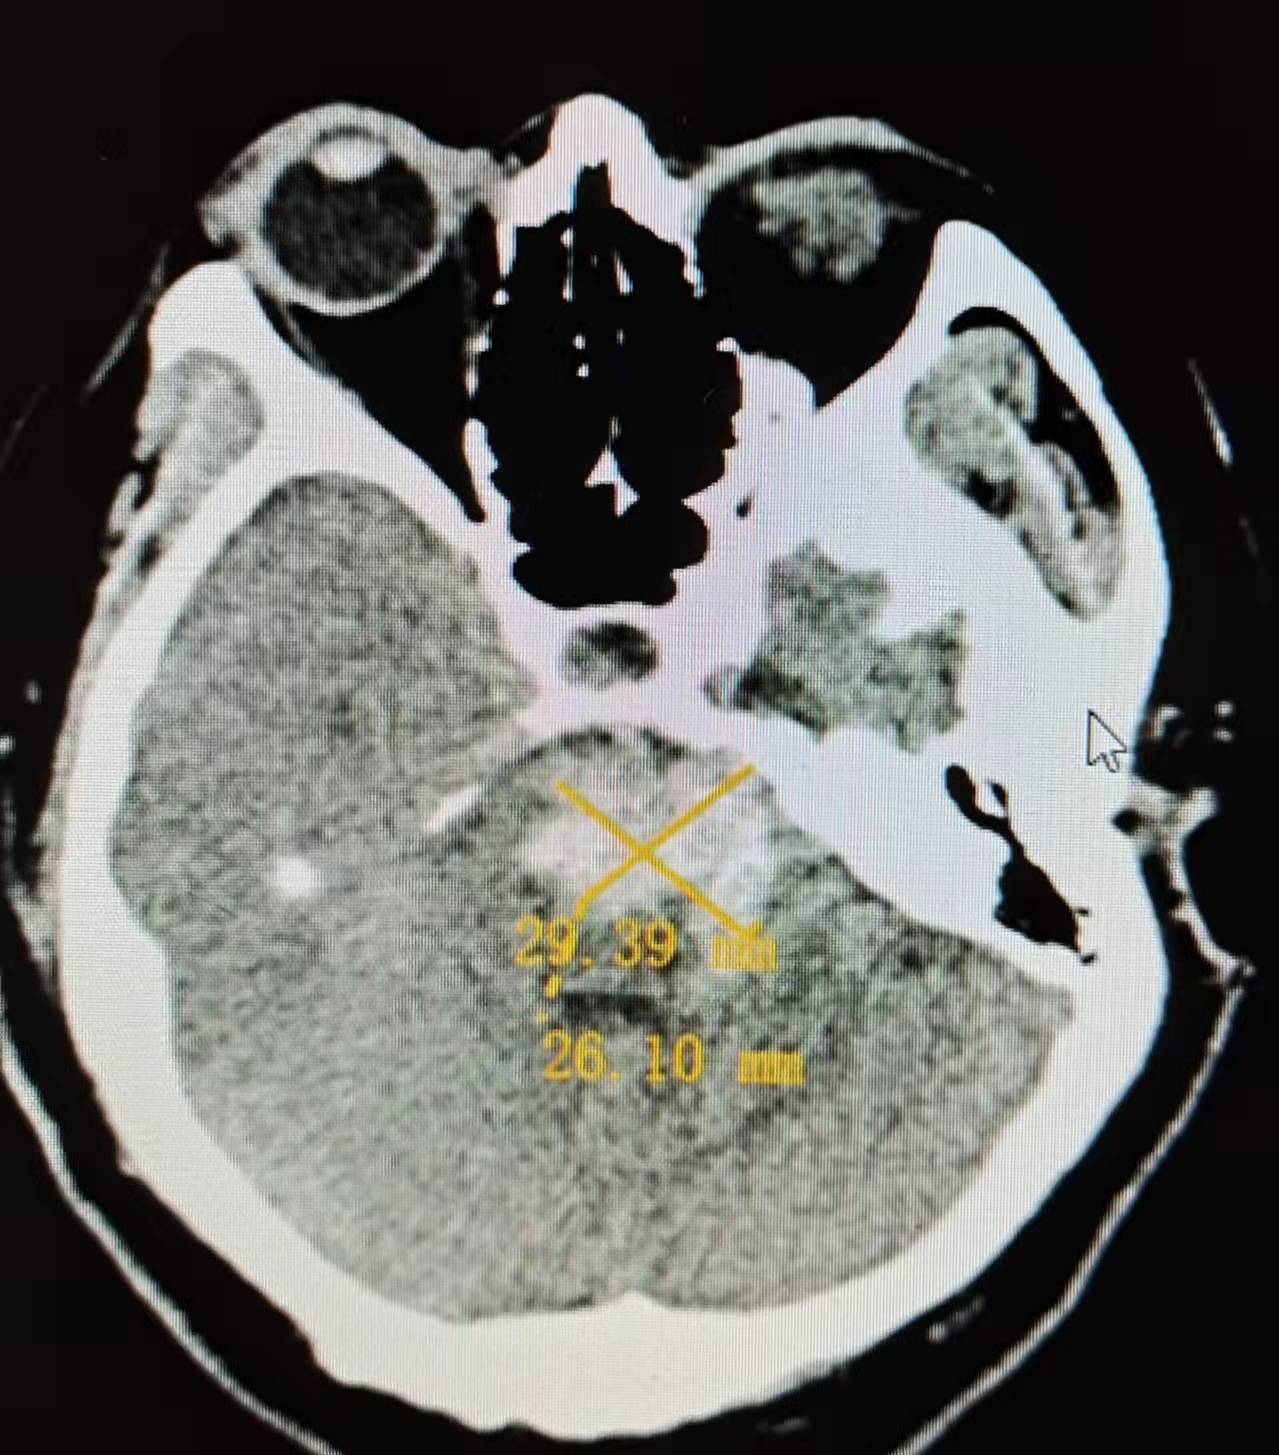

经CT检查诊断为高血压性脑干出血,出血量约13ml(图1),病情极其危重。经积极的术前准备,征得家属同意后,于住院11小时后,全麻下行经枕下脑干血肿微创置管抽吸术+侧脑室外引流术+微创气管切开急诊手术。手术历时1小时零15分钟,术后即刻复查头颅CT,见血肿清除90%(图2)。

图1:术前CT